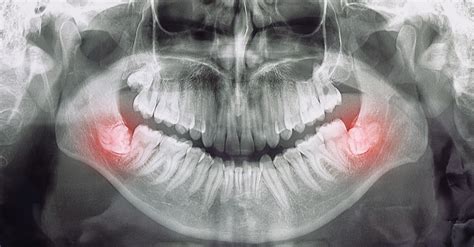

Ocurre cuando un diente no puede emerger completamente porque encuentra un obstáculo o falta de espacio. Las muelas del juicio y los colmillos (caninos) son los más propensos a quedar retenidos bajo la encía. En estos casos el diente puede salir parcialmente o en una posición anómala. Por ejemplo, la muela del juicio puede asomar solo una esquina causando inflamación a su alrededor.

Un diente impactado permanece atrapado en el hueso o la encía, a veces mostrando solo una parte visible. Esto suele deberse a falta de espacio (apiñamiento dental), a que la mandíbula es pequeña o a que el diente está mal posicionado.